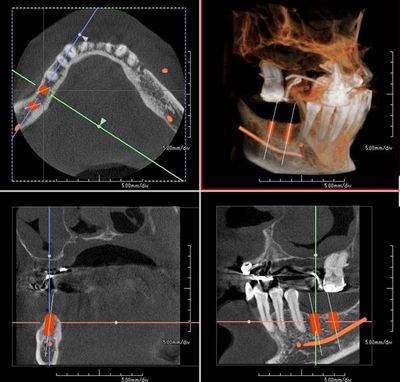

初診時のCTデータにおけるシミュレーションです。

初診時は上顎も部分入れ歯をご使用でしたが

残念なから残存歯は保存不能で総義歯を作製しています。

横に走るオレンジのラインは下歯槽神経管であり、特に奥側は注意が必要です。

手前側(第一大臼歯部分)の断面図です。

骨幅が狭いことと、上顎が総義歯につきレギュラー(Φ4.1mm)を選択します。

フラットニングして短いインプラントを選択することも選択肢としてはありますが

垂直的な骨吸収をきたしている部分をさらにフラットニングすると

歯冠長をさらに長くする結果となりますので見送ります。

奥側(第二大臼歯部分)です。

下歯槽神経管までの垂直的距離が短く、位置づけを慎重に行う必要があります。

ストローマン社のボーンレベルインプラントは最も短いもので8mmですので

スレッドの露出部分をカバーすることを計画し、このポジションを選択します。

下歯槽神経管までの余裕は2mm程度は必要です。